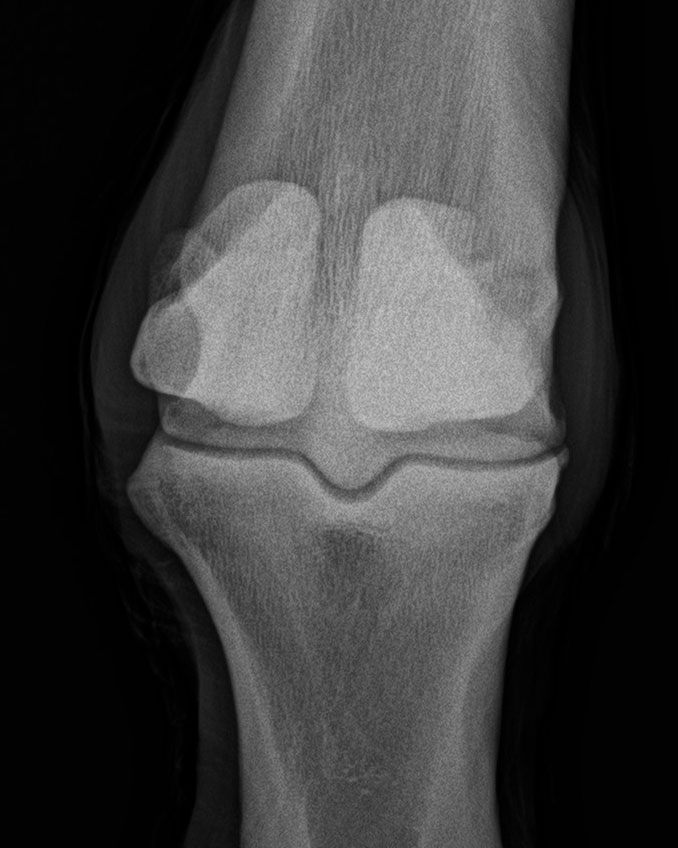

Fesselgelenk - 0°-Aufnahme